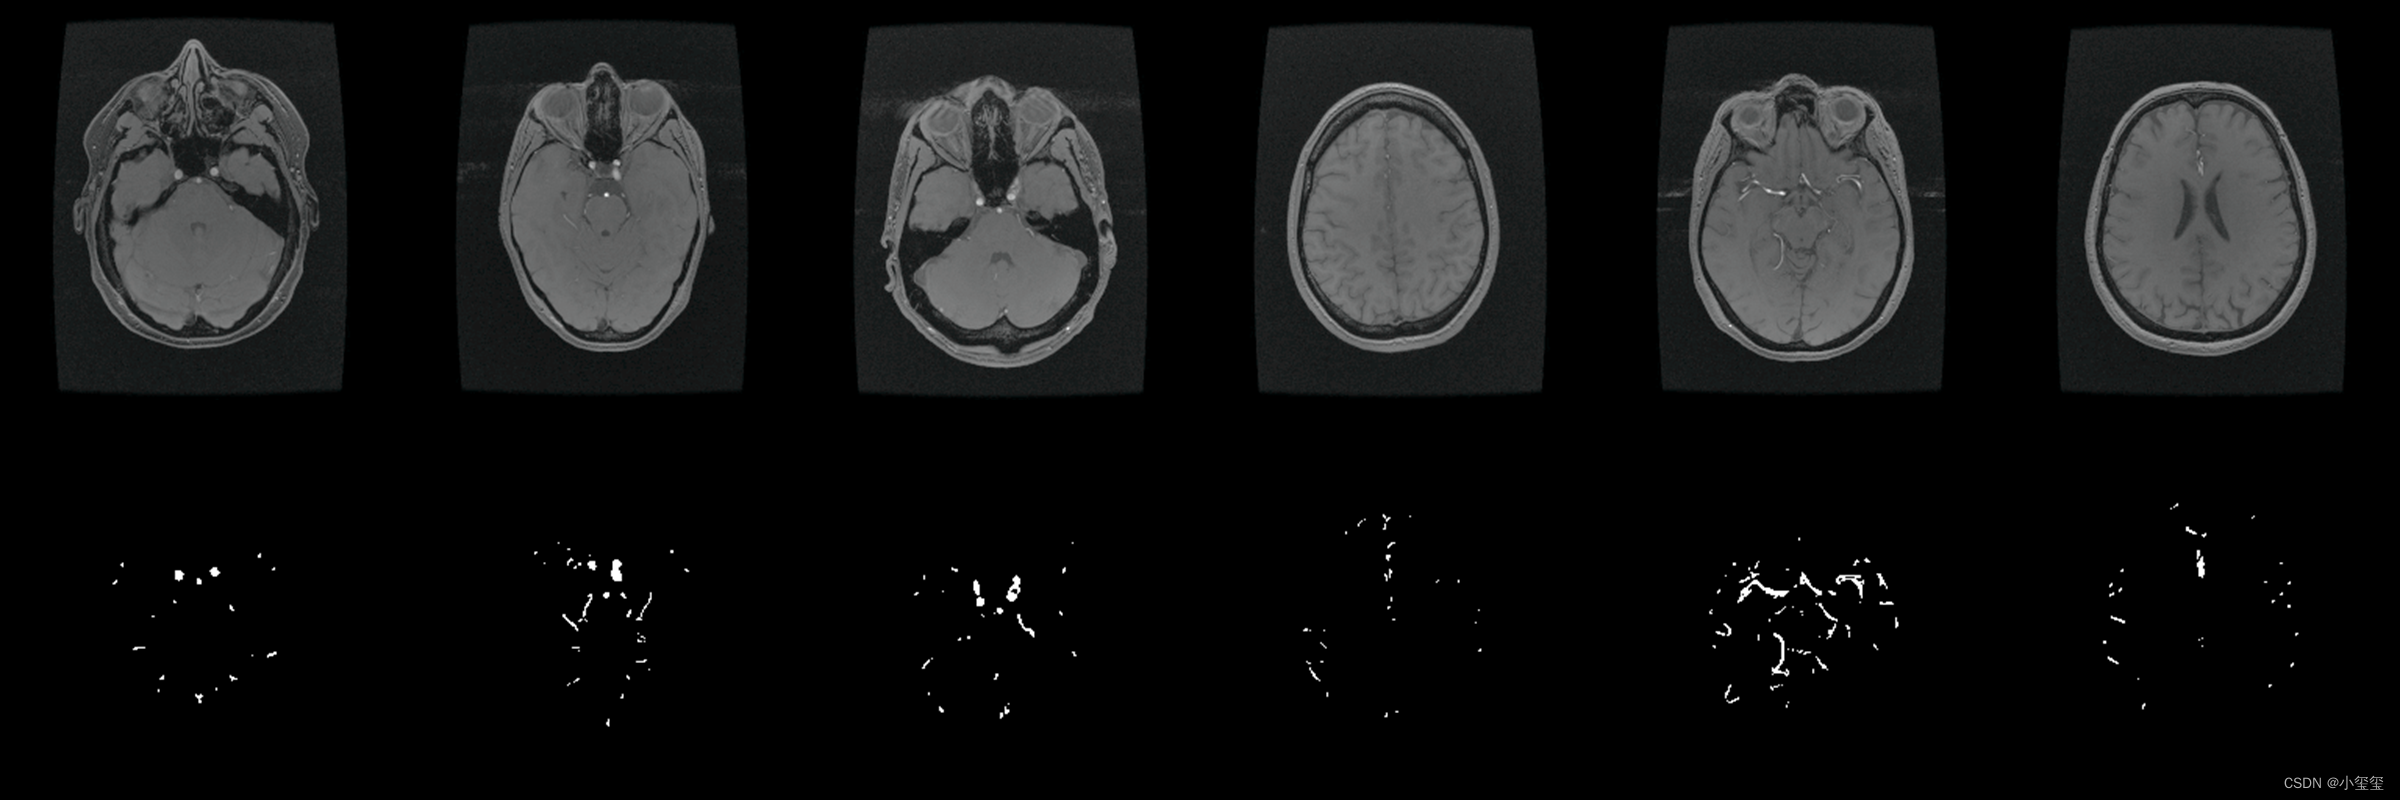

整个流程的演示我以医疗应用为背景,基于UNet完成训练、量化、部署整个流程。PS:之前想以细胞分割来展示,但是GT视觉效果比较密恐,所以找师弟要了一套看来舒服一点的医疗数据集重新训练更换效果图。

- 数据集来自2022年发表在TMI的论文《Attention-Assisted Adversarial Model for Cerebrovascular Segmentation in 3D TOF-MRA Volumes》。数据集实际上是MRA图像,我这里只保留了脑血管GT,用二分类的Unet来介绍整体的部署流程(这里感谢诺师弟的帮助)。